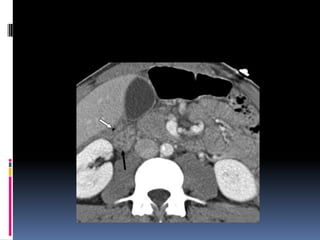

¿LÍQUIDO LIBRE HIPERDENSO? Diagnóstico: RUPTURA VESICAL